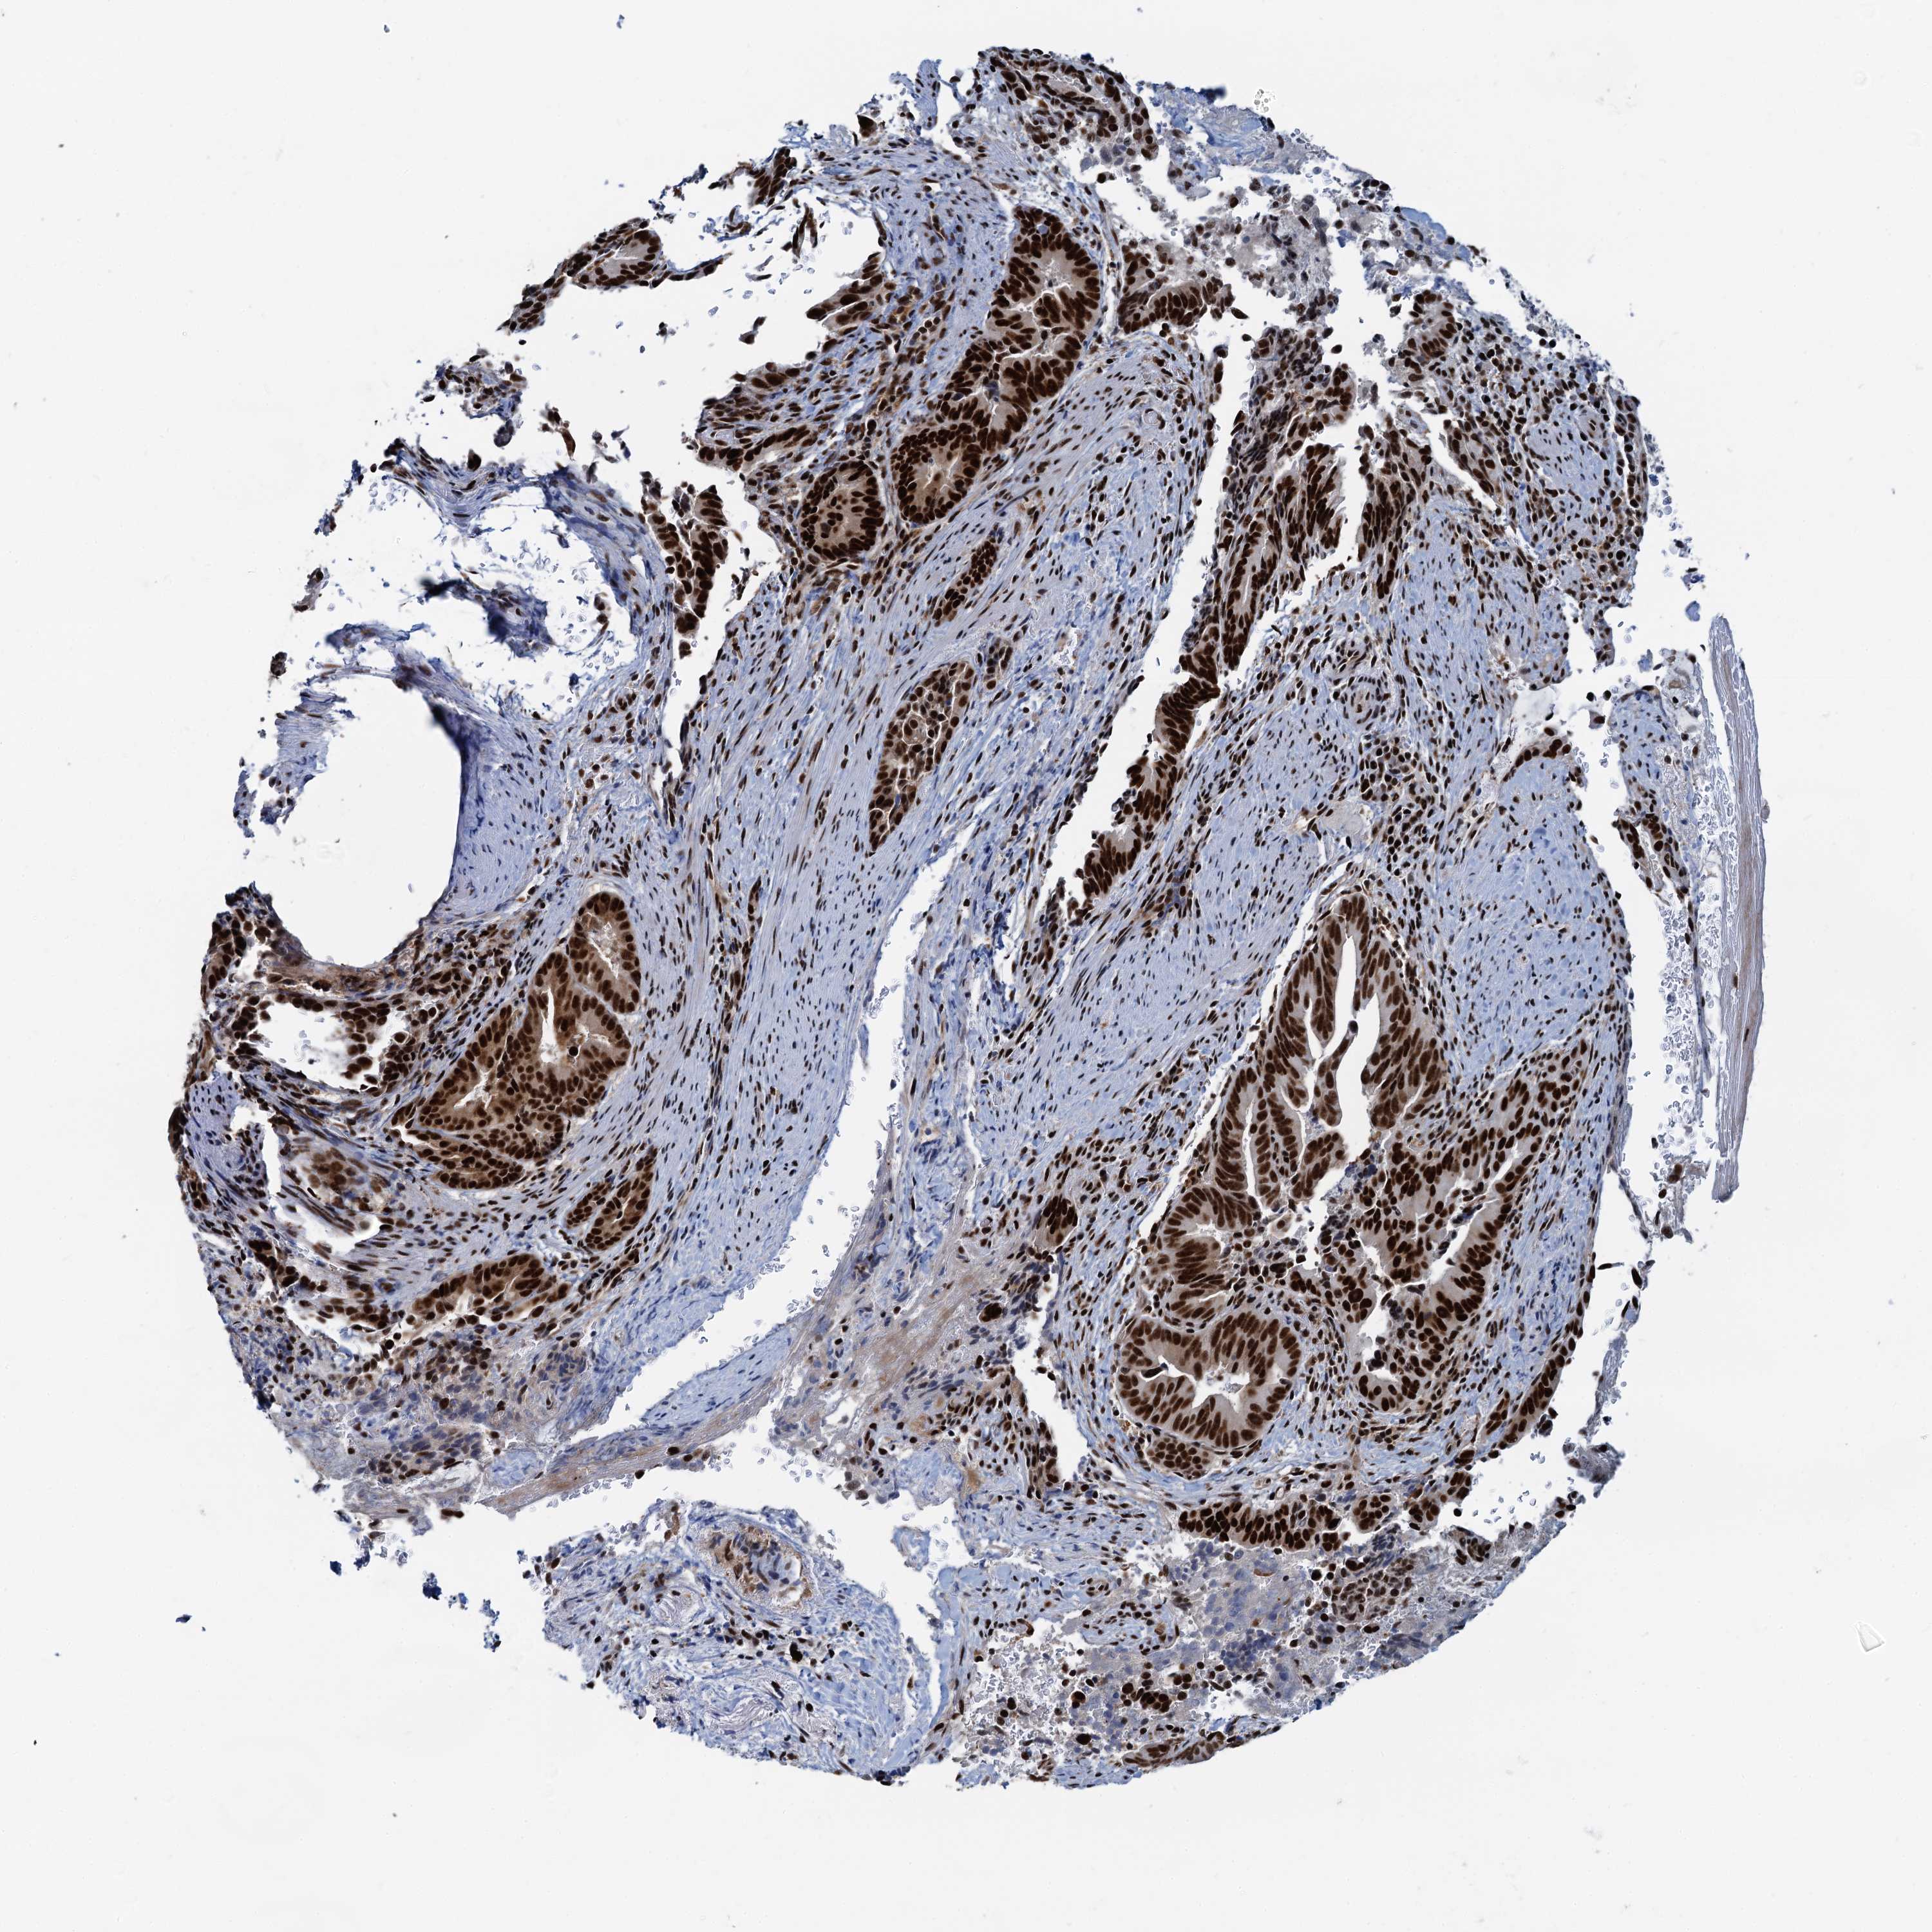

PANCREATIC CANCER - Protein expressioni

A mouse-over function shows sample information and annotation data. Click on an image to view it in a full screen mode. Samples can be filtered based on level of antibody staining by selecting one or several of the following categories: high, medium, low and not detected. The assay and annotation is described here.

Note that samples used for immunohistochemistry by the Human Protein Atlas do not correspond to samples in the TCGA dataset.

Antibody stainingi

Antibody staining in the annotated cell types in the current human tissue is reported as not detected, low, medium, or high, based on conventional immunohistochemistry profiling in selected tissues. This score is based on the combination of the staining intensity and fraction of stained cells.

Each image is clickable and will lead to virtual microscopy that enables deeper exploration of all samples and also displays staining intensity scores, fraction scores and subcellular localization as well as patient and tissue information for each sample.

Antibody HPA040252

Staining

High

Medium

Low

Not detected

Intensity

Strong

Moderate

Weak

Negative

Quantity

>75%

75%-25%

<25%

None

Location

Nuclear

Cytoplasmic/membranous

Cytoplasmic/membranous,nuclear

Adenocarcinoma, NOS